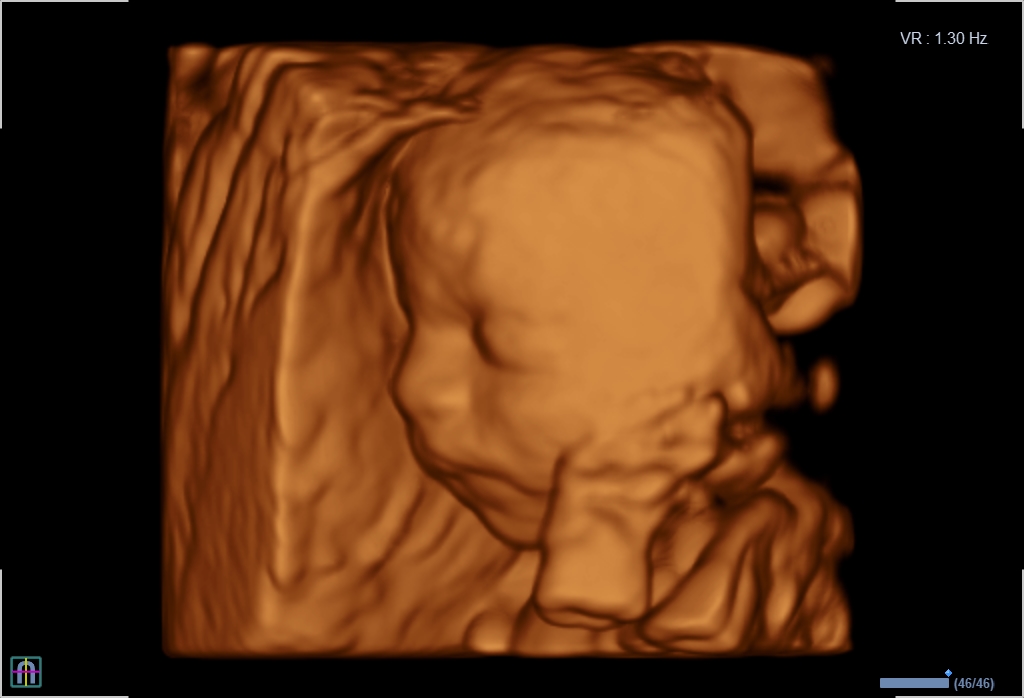

3D/4D-Ultraschall für Schwangere

Ergänzende Sonographie als Wahlleistung

Seit März 2019 steht ein neues 3D/4D-Ultraschallgerät für faszinierende Eindrücke von Ihrem Baby zur Verfügung.

Außer den Fotos können auch 3D/4D Viedeoclips gemacht und auf einem USB-Stick gespeichert werden. So können die Bilder und Clips jederzeit angesehen werden.